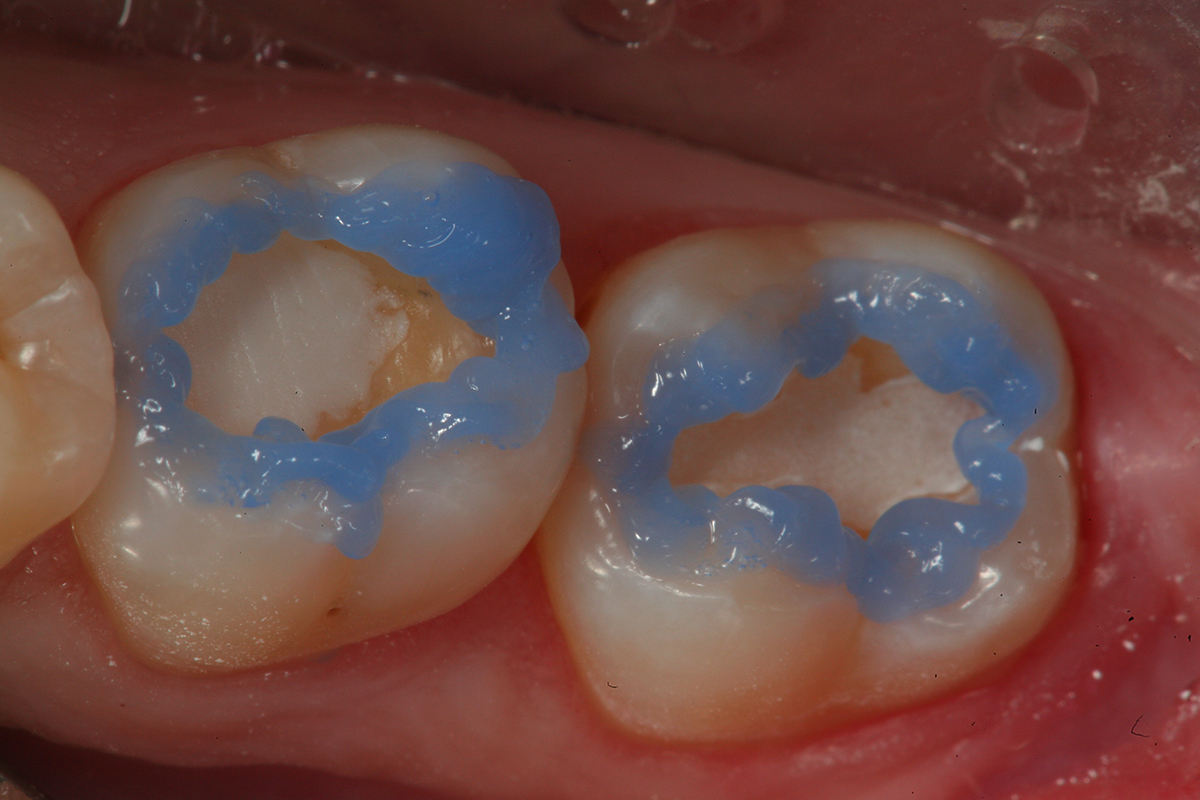

Fig 12. Selective etch of enamel is performed using Select Etch HV® (Bisco Dental Products).

Figure 12